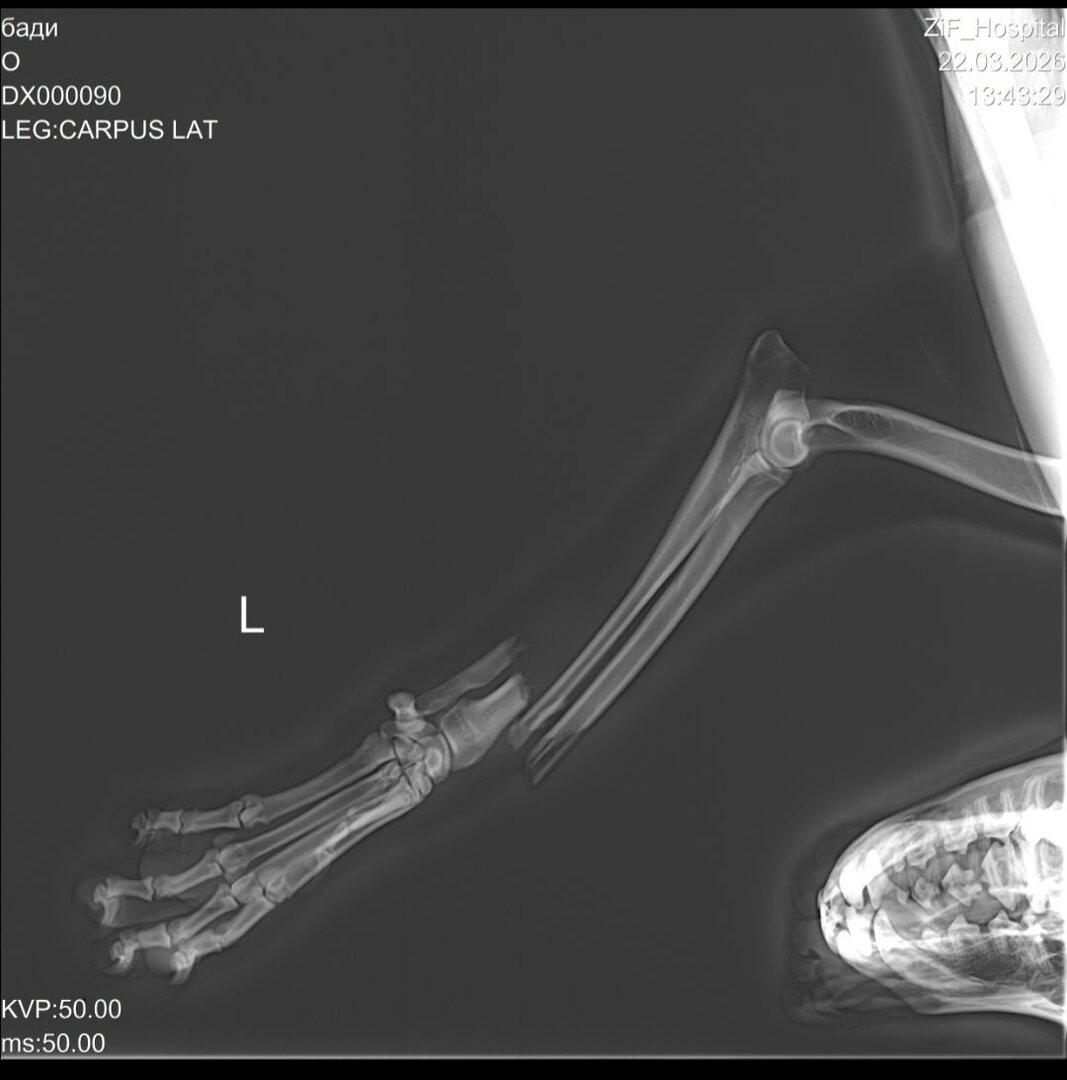

Несчастный случай произошёл 17 марта. Как рассказали очевидцы, машина переехала Бадди переднюю лапу — кость торчала наружу. Собаку отнесли домой. Хозяйка пса зафиксировала перелом палкой и перемотала бинтом.

Конечность кровоточила, а сам пёс без помощи и обезболивающих пролежал дома четыре дня. Неравнодушные соседи написали о ситуации в соцсетях 21 марта и попросили откликнуться волонтёров. Шумилова договорилась с клиникой, собаку привезли на осмотр, после чего владелица написала отказ от питомца.

Ситуация была плачевной, сломаны две косточки. Из-за того, что затянули время и он долго лежал с открытой раной, на лапе начался некроз мягких тканей. От боли пёс даже пытался отгрызть себе лапу...

Мы с Бадди были на приёме у хирурга-ортопеда, доктор обещает полное восстановление и полноценную жизнь. Сейчас собачка находится в клинике на стационаре, ожидая операцию, стоимость которой — 55 тысяч рублей. Малышу установят внешний фиксатор и спицы, так как переломы очень сложные. Без помощи неравнодушных калининградцев мы не справимся. У нас в клинике огромные долги... Пёс молодой, очень красивый и добрый. Его жизнь только начинается. Помогите, пожалуйста, Бадди сохранить лапку», — призывает Шумилова.